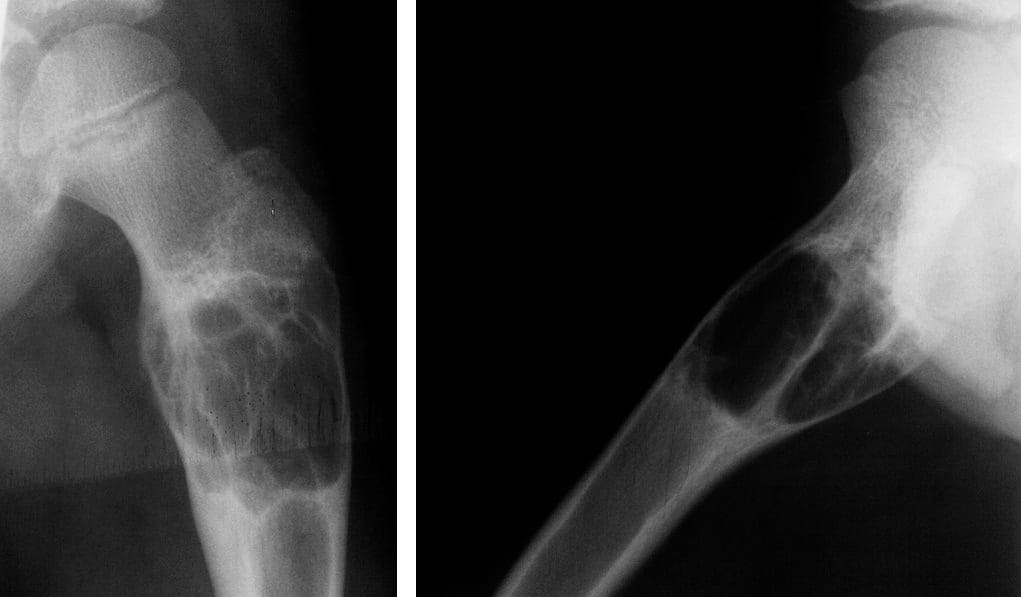

Для подтверждения диагноза проводится регулярное рентгенологическое исследование пораженной кости. При этом важно установить фазу патологического процесса. В фазе остеолиза на снимке обнаруживают разрежение костной ткани, в фазе отграничения – полость с ячеистым рисунком и плотной стенкой, в фазе восстановления – полость или зоны уплотнения костной ткани.

Для уточнения диагноза наибольшее значение имеет рентгенологическое исследование. При этом на снимках обнаруживаются следующие изменения:

- в фазе остеолиза – бесструктурный очаг с сохраненной надкостницей (тонкой соединительнотканной пленкой, которая покрывает кость в виде футляра);

- в фазе отграничения – между зоной поражения и здоровой костью формируется участок склероза (уплотненной костной ткани), мягкие ткани вокруг патологического очага также уплотняются и уменьшаются в размере;

- в фазе восстановления – обнаруживается полость либо участок разрастания костной ткани.